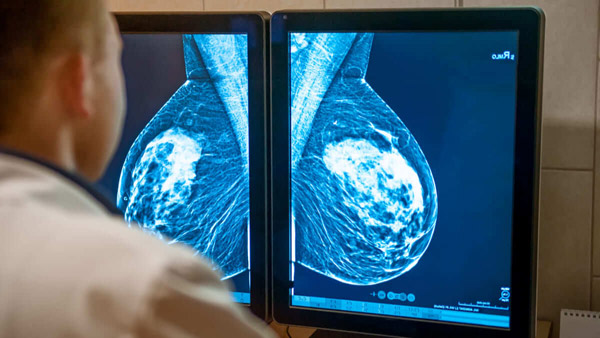

晚期乳腺癌多線治療失敗怎么辦?全新免疫療法帶來新曙光

乳腺癌

世界衛(wèi)生組織數(shù)據(jù)顯示,乳腺癌已取代肺癌成為全球第一大腫瘤,我國乳腺癌發(fā)病率也在逐年攀升。

我國每年大約新增乳腺癌患者42萬人,且發(fā)病率每年遞增3%到4%。